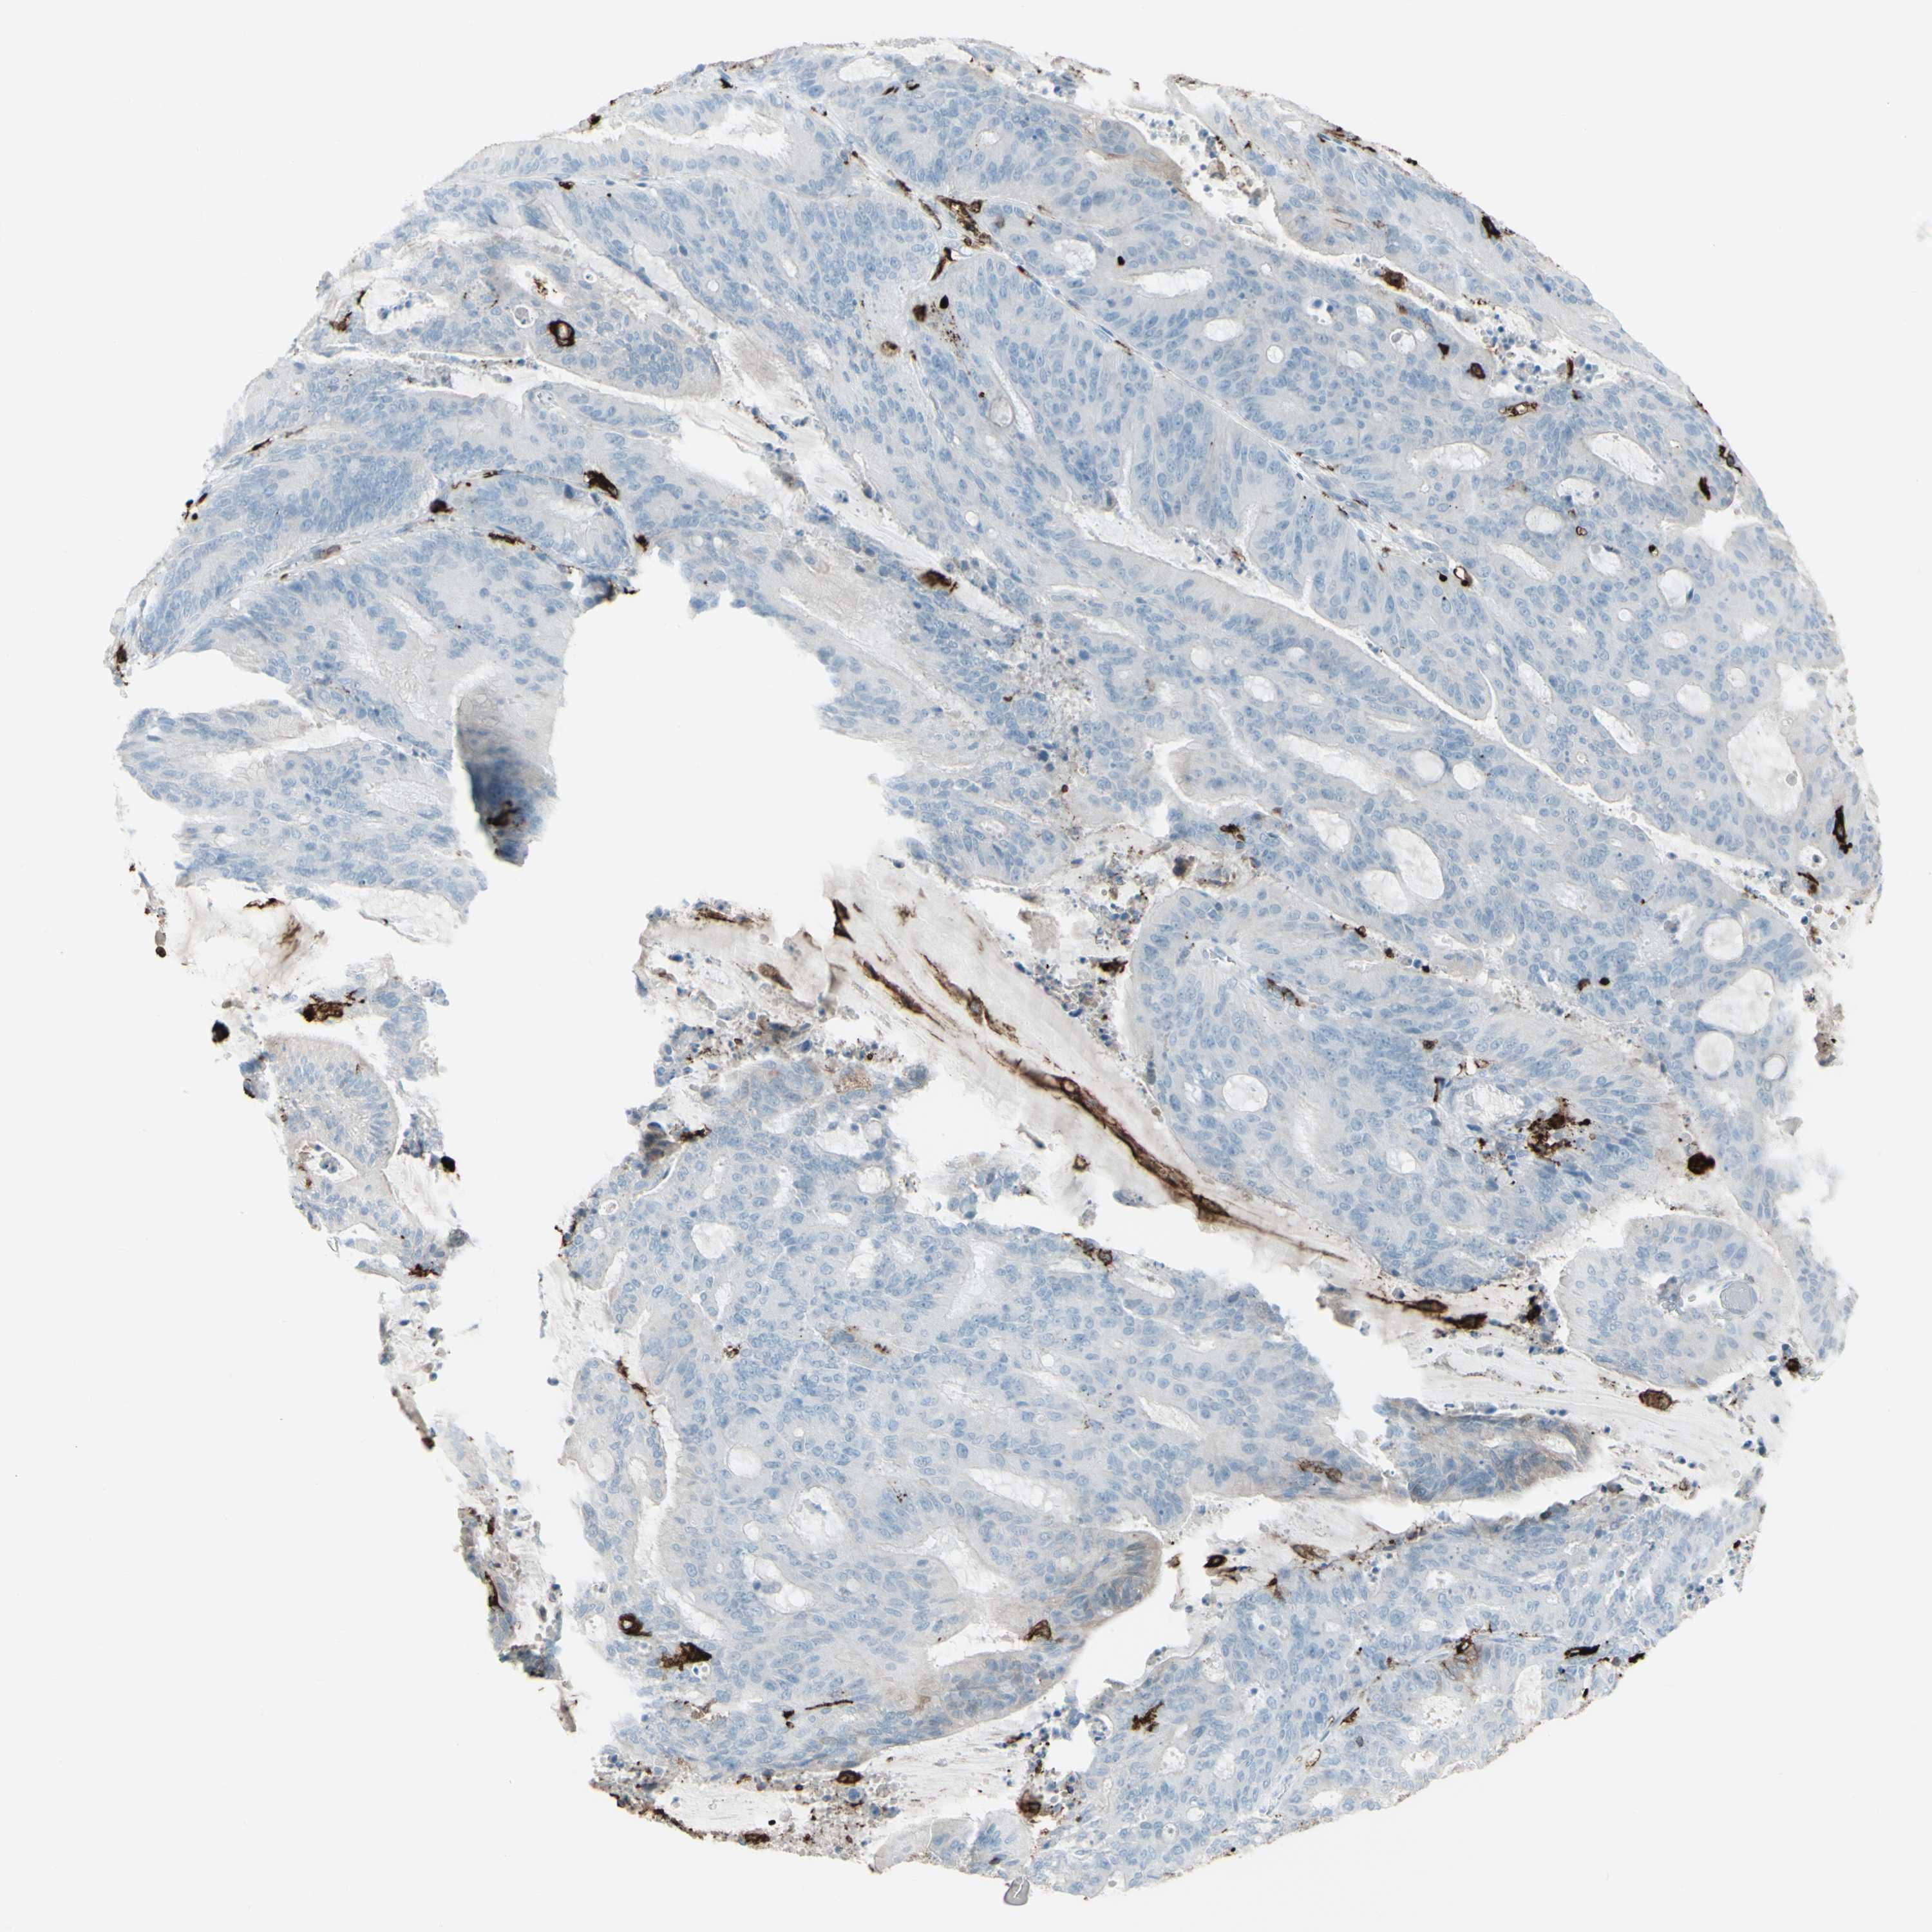

LIVER CANCER - Protein expressioni

A mouse-over function shows sample information and annotation data. Click on an image to view it in a full screen mode. Samples can be filtered based on level of antibody staining by selecting one or several of the following categories: high, medium, low and not detected. The assay and annotation is described here.

Note that samples used for immunohistochemistry by the Human Protein Atlas do not correspond to samples in the TCGA dataset.

Antibody stainingi

Antibody staining in the annotated cell types in the current human tissue is reported as not detected, low, medium, or high, based on conventional immunohistochemistry profiling in selected tissues. This score is based on the combination of the staining intensity and fraction of stained cells.

Each image is clickable and will lead to virtual microscopy that enables deeper exploration of all samples and also displays staining intensity scores, fraction scores and subcellular localization as well as patient and tissue information for each sample.

Antibody HPA011078

Staining

High

Medium

Low

Not detected

Intensity

Strong

Moderate

Weak

Negative

Quantity

>75%

75%-25%

<25%

None

Location

Nuclear

Cytoplasmic/membranous

Cytoplasmic/membranous,nuclear

Cholangiocarcinoma

Carcinoma, Hepatocellular, NOS